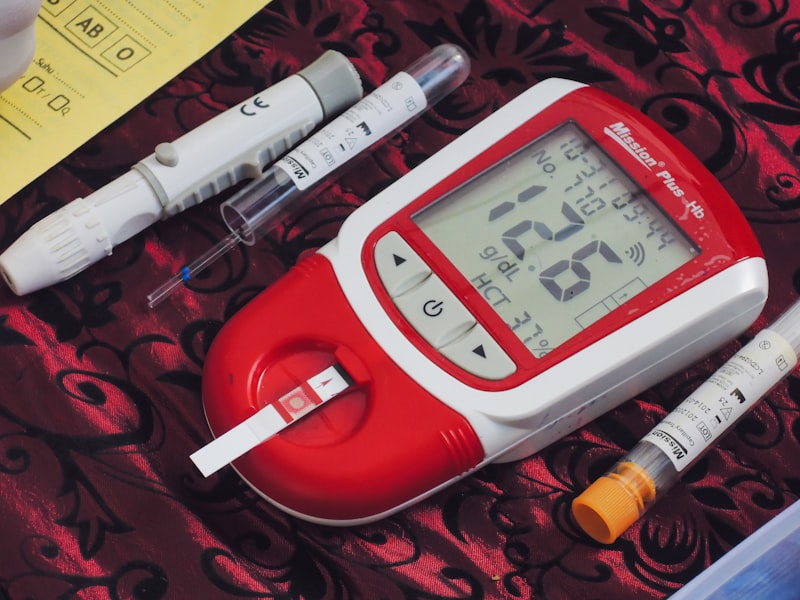

Chronic Disease Management

Ongoing, personalized management of chronic conditions with regular monitoring, medication adjustments, and lifestyle counseling to optimize your health outcomes.

- Diabetes management

Phlebotomy & Lab Services

On-site blood sample collection and urine specimen services for laboratory testing. Convenient in-clinic sample collection saves you a separate trip to the lab.

- Routine blood work

- Fasting glucose and lipid panels